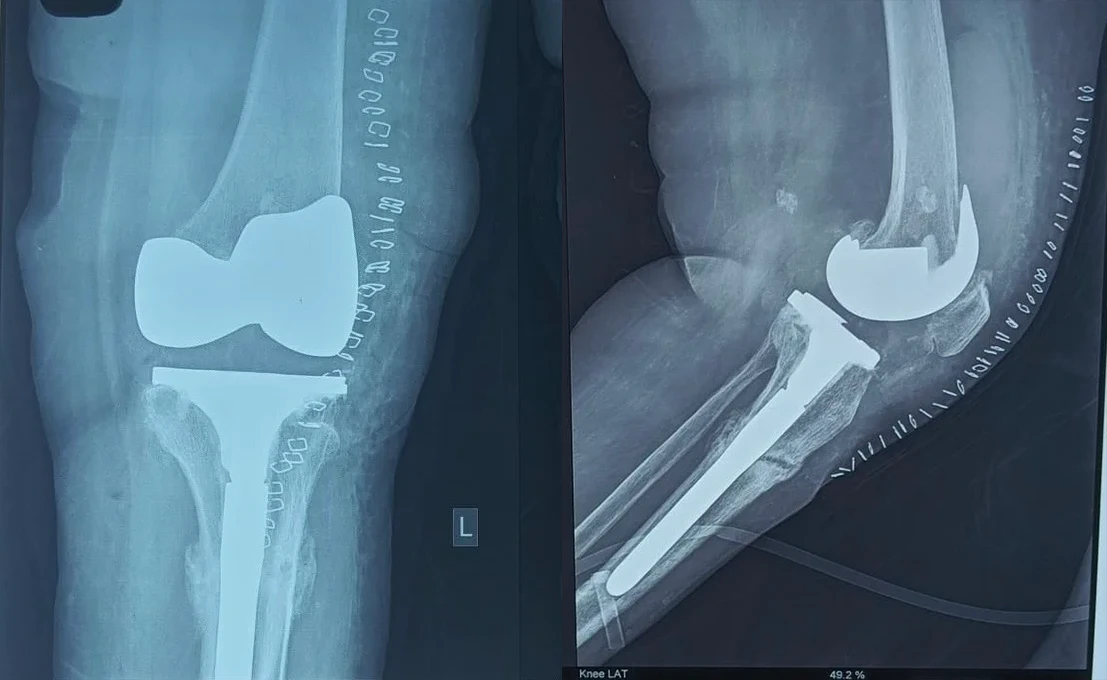

Stress Fracture of Tibia with Rigid Varus Deformity

Post-Op X-Ray

Tibial Component with Extender

Implant Oxinium